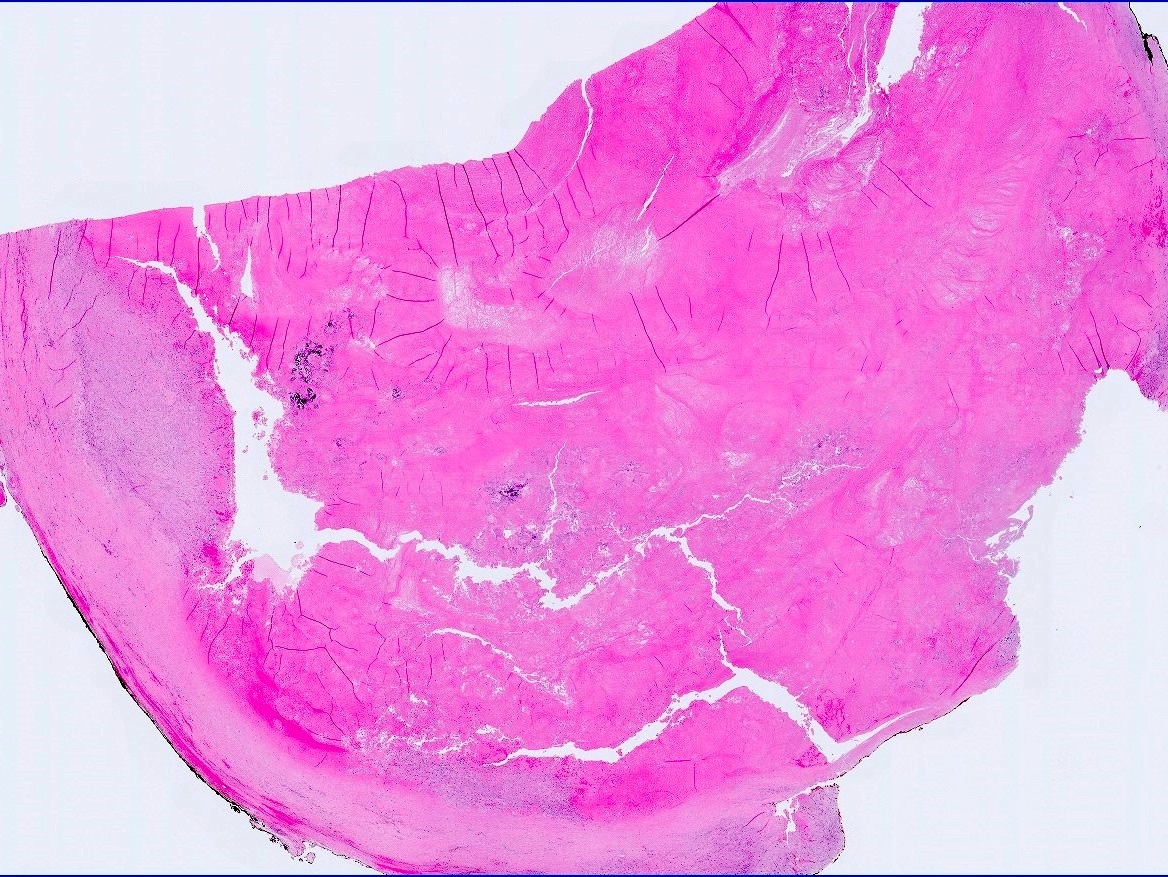

Gross images

Contributed by Debra L. Zynger, M.D.

Testis & epididymis - Staging Board review style question #2

The postpubertal teratoma shown in the gross photo is 1.7 cm and is confined to the testis and did not have lymphovascular invasion. Which is the correct pT category?

Board review style answer #2

A. pT1. Postpubertal germ cell tumors that are confined to the testicular parenchyma and lack lymphovascular invasion are pT1, pT1a or pT1b. Pure seminoma is stratified as pT1a and pT1b based on a 3 cm threshold. Nonpure seminomas are not stratified and therefore this tumor is pT1.

Comment Here Reference:

Testis & epididymis - Staging